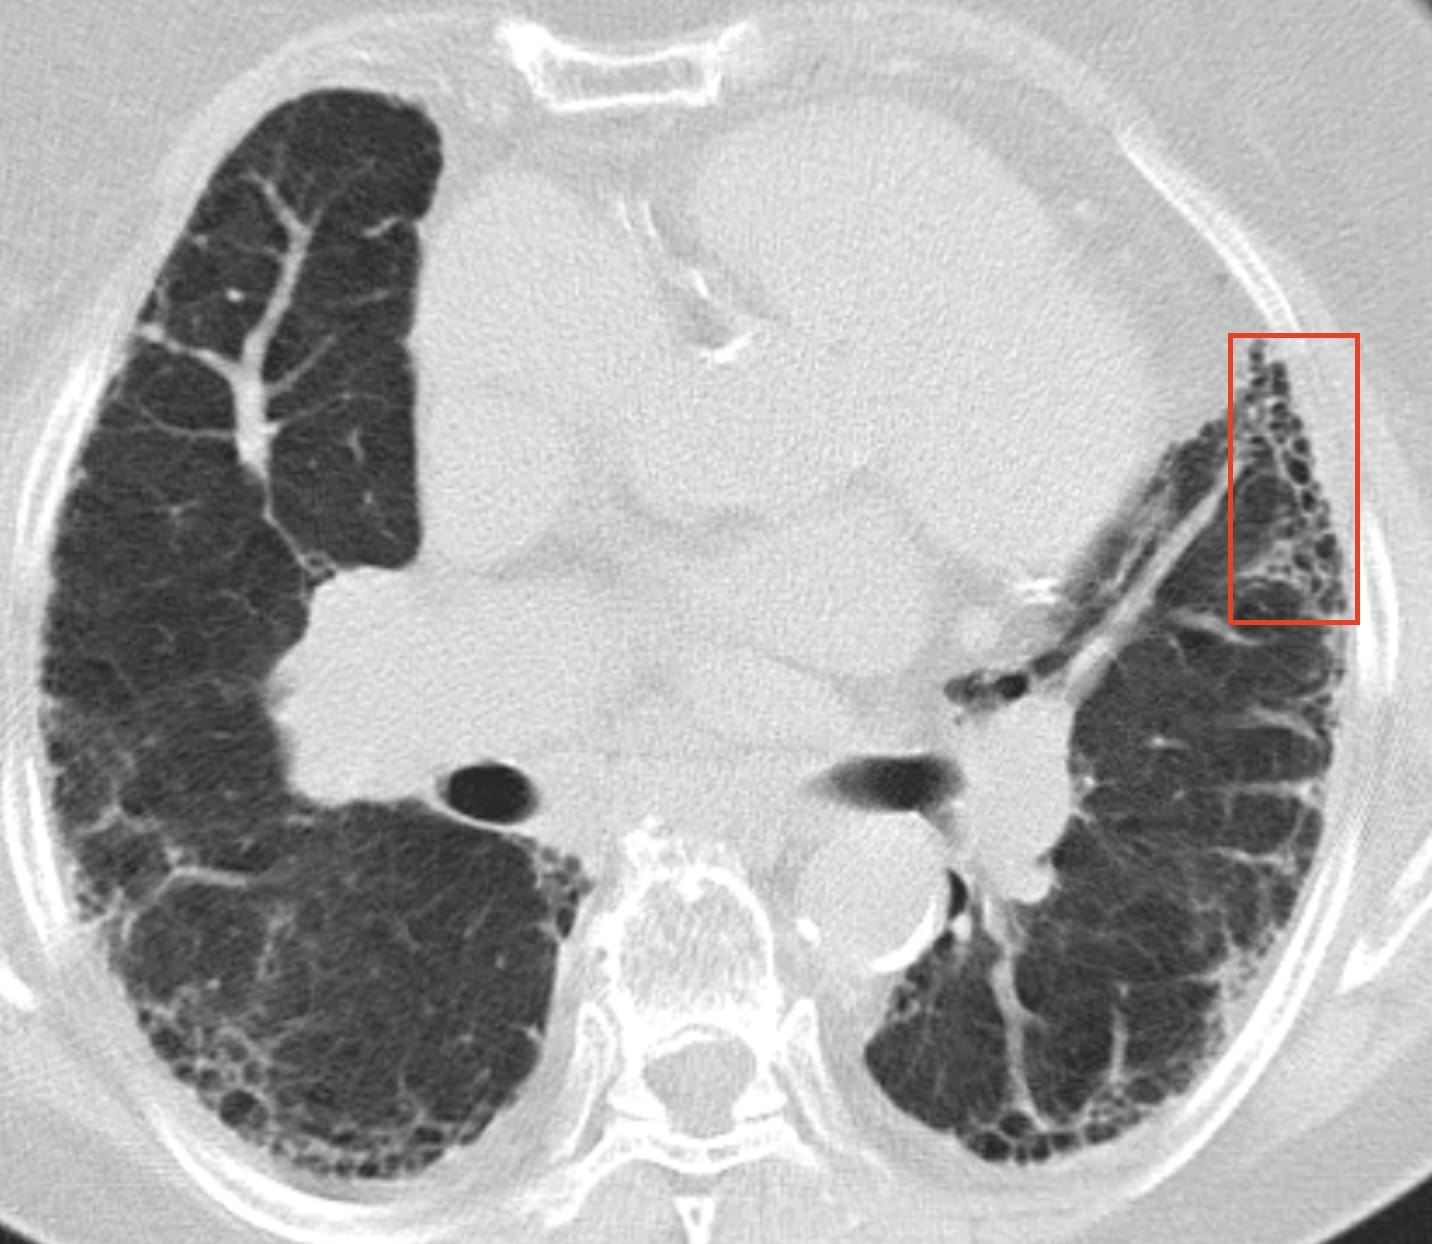

- Usual Interstitial Pneumonia